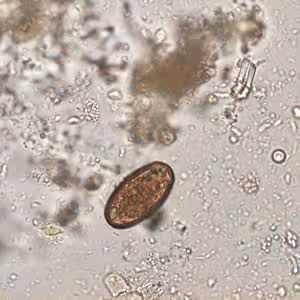

A huntsman killed a bear and prepared it for eating and freezing by cutting it into roasts, steaks, and grinding the trimmings. Later that same day, he ate a burger made from some of the fresh meat and cooked rare. Approximately two and a half to three weeks later, the hunter experienced fever, diarrhea, and muscle pain.